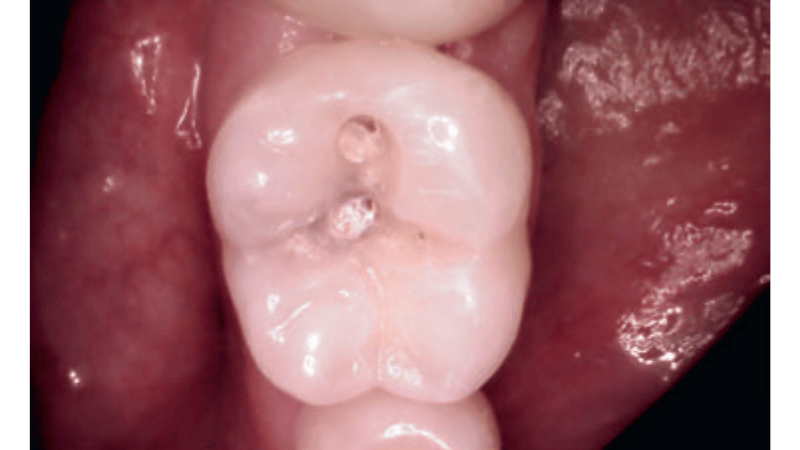

Streszczenie: Próchnica bruzd to często niedoceniany problem kliniczny, szczególnie we wczesnym stadium rozwoju, gdy zmiany są subtelne i mogą nie być widoczne bez odpowiednich narzędzi diagnostycznych. W artykule omówiono trudności w diagnostyce oraz komunikacji z pacjentem, oparto się na dostępnych źródłach naukowych i przedstawiono przypadek kliniczny z własnej praktyki.

Summary: Fissure caries is often an underestimated clinical issue, especially in the early stages, when changes are subtle and not visible without appropriate diagnostic tools. This article discusses diagnostic and communication challenges, includes references to scientific literature, and presents a clinical case from the author’s practice.